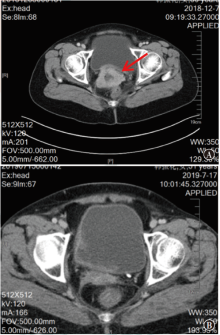

晚期及复发性宫颈癌治疗方式有限,预后差,免疫治疗为近期备受关注的一种宫颈癌治疗手段。现报道1例综合阳性评分为100分的宫颈癌复发患者免疫治疗疗效,该患者单靶点免疫药物治疗10个月余出现疾病进展,考虑免疫耐药,通过分析该患者的临床资料,并复习相关文献,以提高对宫颈癌免疫治疗及耐药机制的认识。